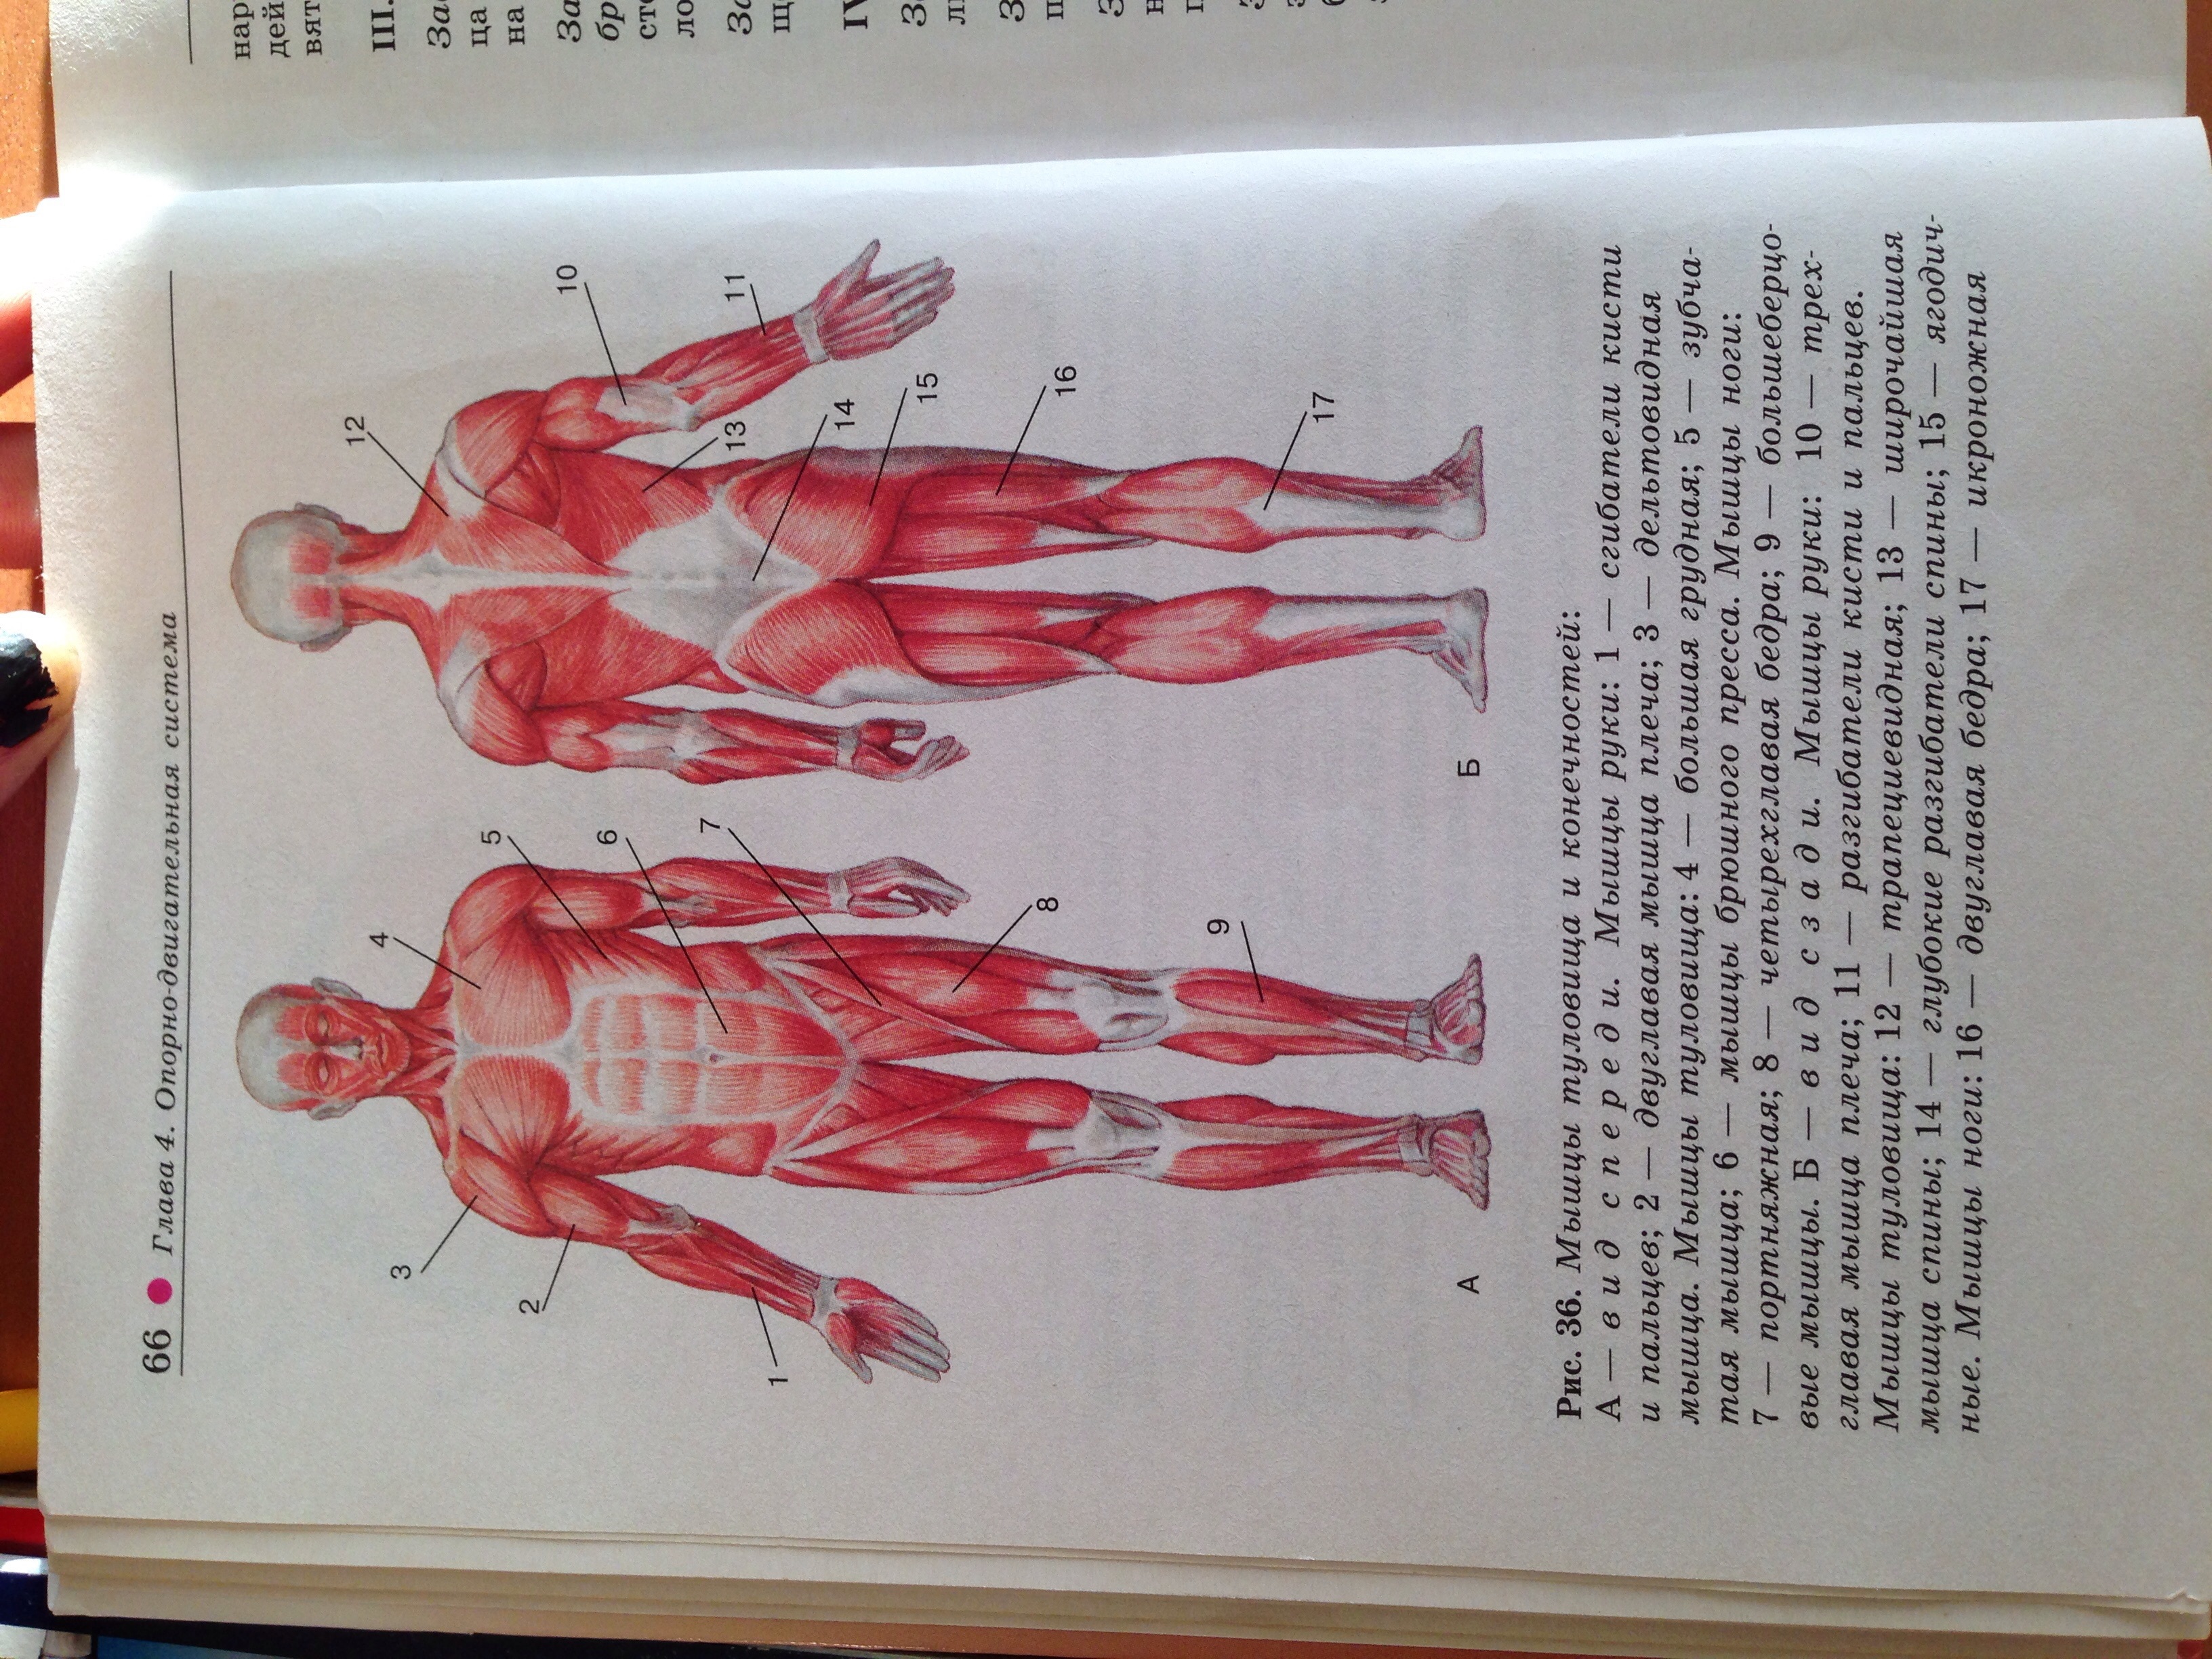

Свойства мышц человека: Основные характеристики

Раздел: Объективный взгляд